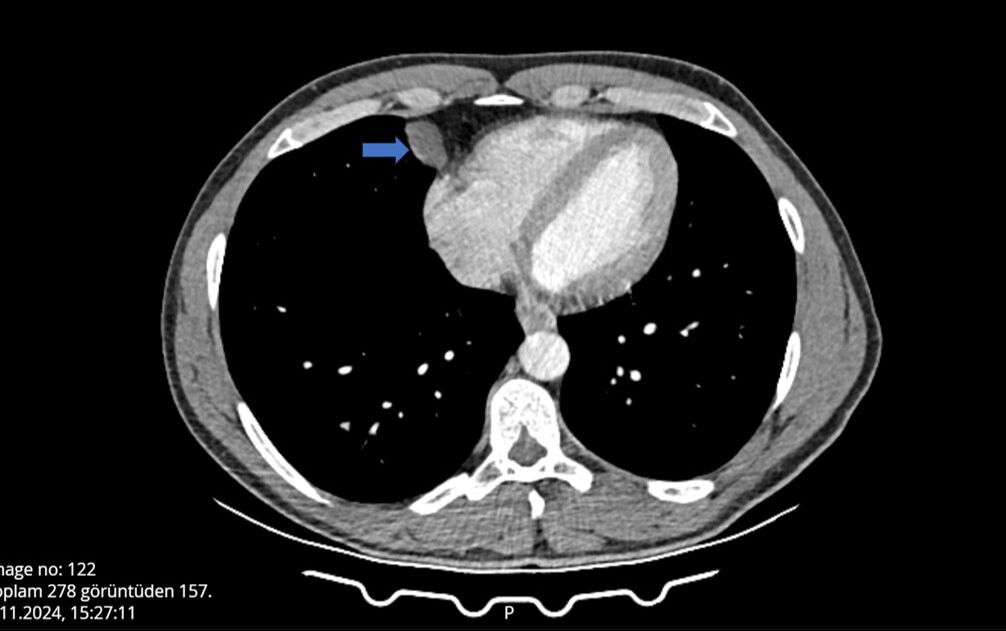

Öksürük ve hapşırık krizine tutulan ve bu nedenle grip olduğunu düşünen adam hastaneye başvurdu, yapılan kontroller sonrası hayatının şokunu yaşadı. Akciğeri ile kalbi arasında kist olduğunu öğrenen adam, 10 dakikalık operasyon sonucu sağlığına kavuştu.

Burada tomografisi çekilen Can'ın, akciğeri ile kalbi arasında bir kist olabileceği belirtildi. Can, çevresindekilerin tavsiyesi üzerine detaylı araştırma ve inceleme için Antalya Eğitim ve Araştırma Hastanesine başvurdu. Gerekli tetkikleri yapılan Ömer Can'ın, belirtilen bölgesinde yaklaşık 2 santimlik bir kist olduğu tespit edildi ve hemen ameliyata alındı.

Antalya Eğitim ve Araştırma Hastanesi Göğüs Cerrahi Kliniği Eğitim Sorumlusu Doç. Dr. Muharrem Özkaya ise hastanın çekilen tomografisinde, akciğerin altında, kalbin yanında perikardiyal kisti bulunduğunu ve VATS yöntemiyle iki delikten girerek kisti aldıklarını söyledi.